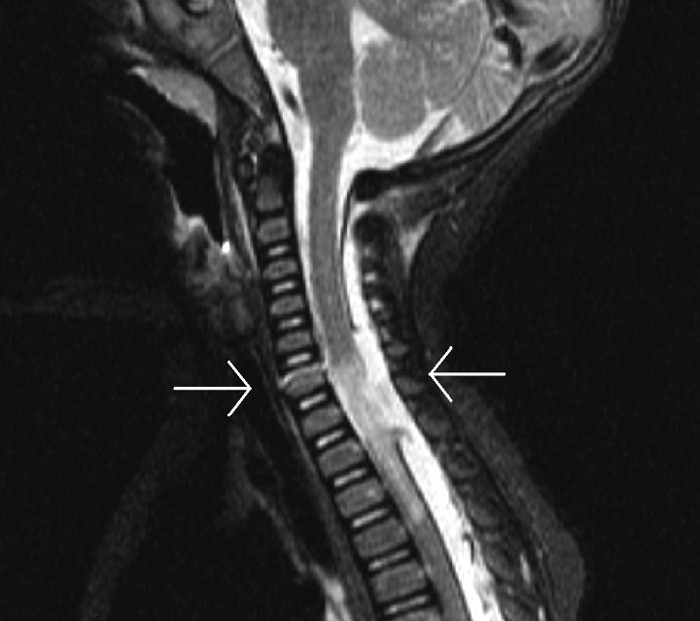

Da gutten var seks måneder gammel, ble han innlagt i sykehus etter å ha vært involvert i en alvorlig bilulykke. CT av hodet viste små, inoperable blødninger subduralt over høyre hjernehalvdel og subaraknoidalt over venstre pannelapp. MR av ryggsøylen avdekket en skade på ryggmargen fra nivå C6 til TH4, en rift i dura fra nivå C6 til TH2 og et brudd i ryggvirvel C6 (fig 1). Nakkeskaden ble betraktet som ustabil, men på grunn av barnets alder og størrelse kunne man ikke tilrettelegge nakkekrage. Det ble anbefalt skånsom behandling av nakken, med særlig vekt på å unngå fleksjon og ekstensjon.